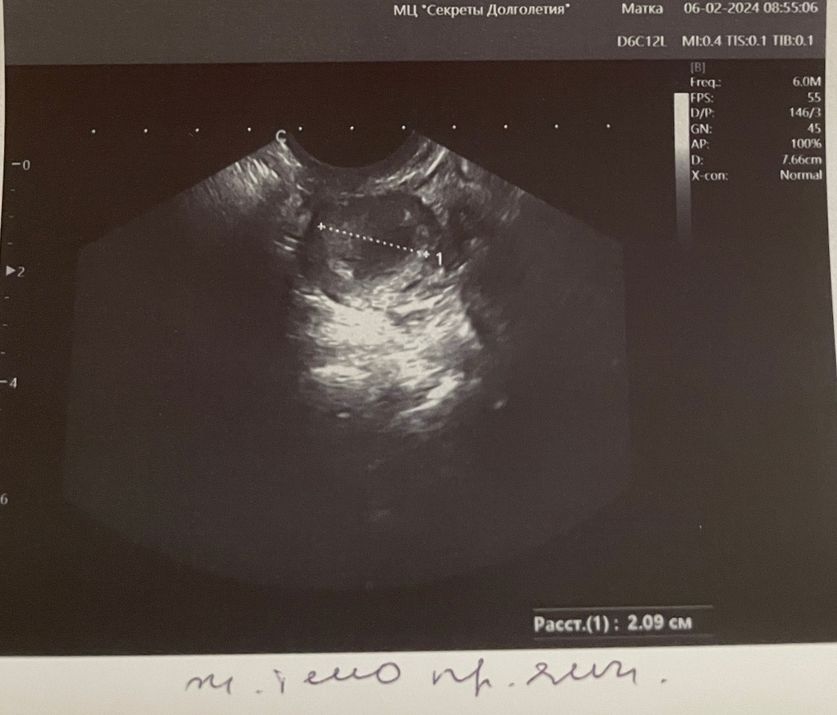

После очередного пролета и праздников первый раз на узи я пошла на 16 ДЦ, после положительного теста на овуляцию (1 фото)

УЗИ 16 ДЦ

Эндометрий 0,6 см трехслойный (тонкий)

Правый яичник - однокамерная киста 26 мм